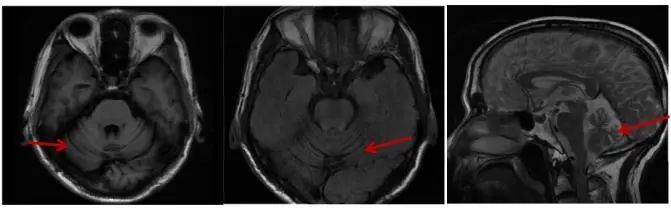

1.1 先证者 男,61岁,因“言语含糊伴行走不稳3年余”入院,主要表现为3年前出现言语含糊伴行走不稳、左足外侧麻木,无饮水呛咳、吞咽困难等,当时脊髓小脑性共济失调评估与评级量表(scale for the assessment and rating of ataxia,SARA)评分3.5分,未予特殊治疗,随后上述症状进行性加重,伴头晕、晨起下肢趾背及手掌尺侧麻木,偶有饮水呛咳,睡眠欠佳。既往有双膝关节疼痛病史。查体阳性体征:言语含糊,双眼右视时水平眼震,双侧指鼻试验欠稳准、右侧为甚,双侧跟膝胫试验欠稳准、右侧为甚,闭目难立征欠稳,步距宽,行走不稳,双侧弓形足、右侧为甚,四肢腱反射活跃,右侧双划征可疑阳性,SARA评分12分。辅助检查:3年前入院时诱发电位、肌电图未见异常,四肢周围神经电图:左L5、S1或其周围支神经损害,头颅MRI:脑白质轻度脱髓鞘改变,小脑萎缩(图1)。此次入院诱发电位、肌电图、神经电图、皮肤交感反应、脑电图、痴呆量表等均无明显异常,头颅MRI见小脑明显萎缩,基因测序:CACNA1A CAG重复次数为 22 次(图2),在全突变范围内。诊断为脊髓小脑性共济失调 6型。

Fig.1 MRI T1, T2and sagittal maps of patient, 2023

图1 患者 2023年头颅MRI T1、T2及矢状位图 见小脑明显萎缩

SCA6型在我国属于较为少见分型(约1.7%),该病临床特征为成年发病、缓慢进展的小脑共济失调、构音障碍和眼球震颤,发病年龄19~73岁,随病情发展可出现吞咽困难和窒息[4],病理特点为小脑萎缩而无脑干萎缩。本例患者首发症状为言语含糊伴行走不稳,随后逐渐进展出现头晕、饮水呛咳、眼球震颤等症状,属临床症状较为典型病例,头颅MRI见小脑明显萎缩。其父发病具体年龄无法追溯,据先证者言约70岁发病,症状相似,其女27岁,为无症状基因携带者,此家系暂符合遗传早现现象,但因病例数少,且其女尚未发病,还需进一步追踪验证。